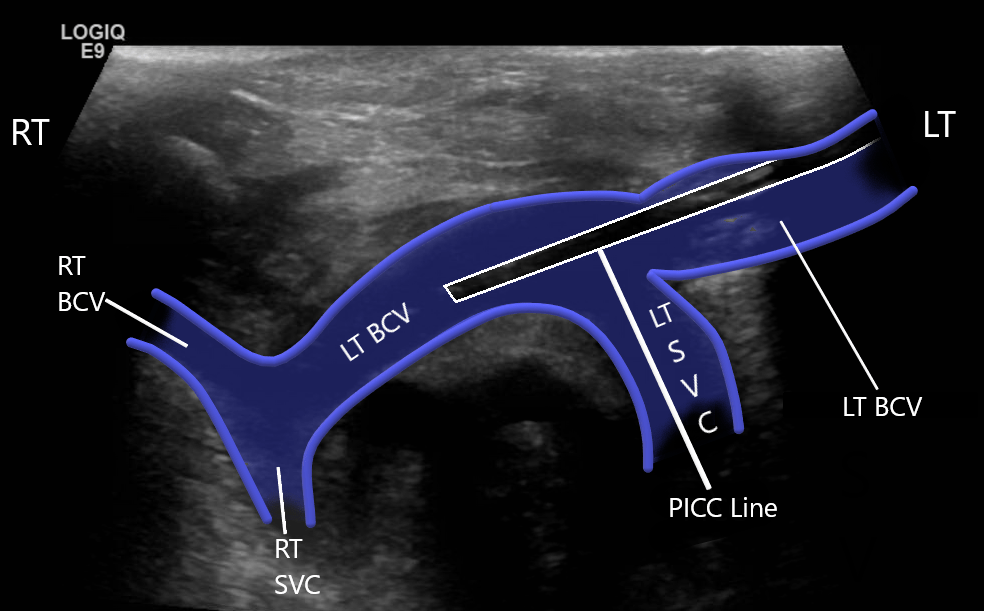

Thrombosis of the right innominate vessel with indwelling catheter